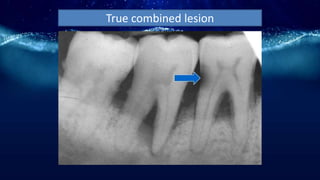

Periodontitis associated with

Combined lesions

True combined lesion